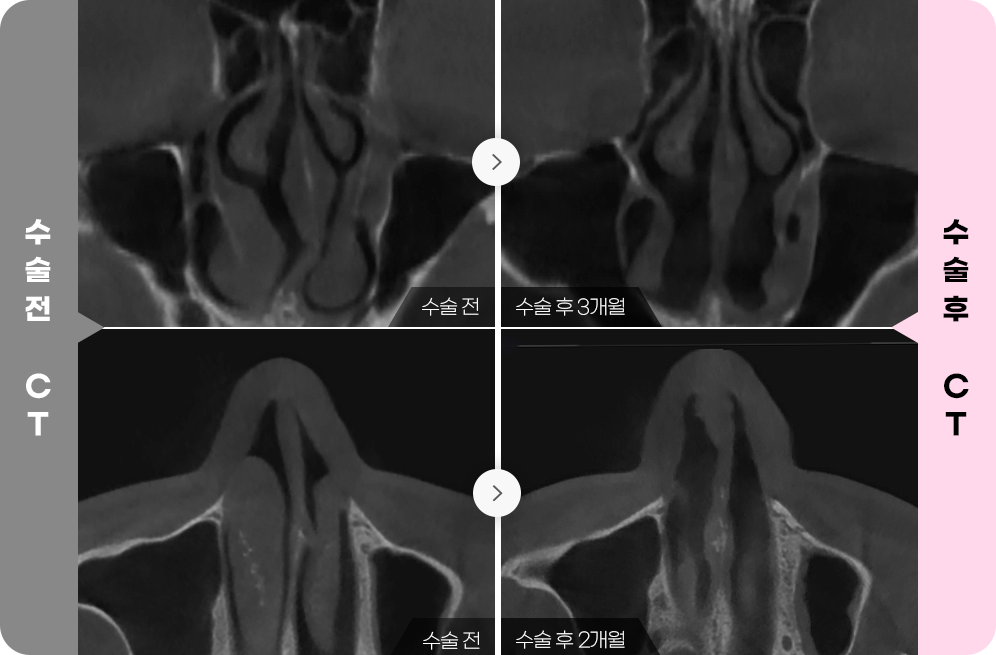

수술 전

코 내부의

기능적 문제를

3D-CT로

정확히

CHECK.